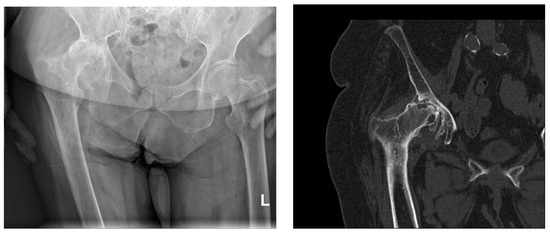

4. Radiological Characteristics of Osteoarthritis